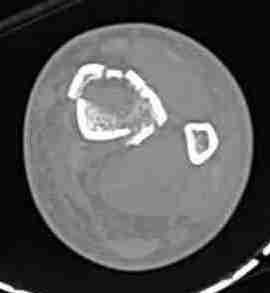

При высокоскоростных переломах редко можно встретить изолированную травму пилона, и в моей практике изолированные травмы большая редкость, поэтому, как дополнение к обсуждаемой теме, решил представить свежий, двухдневной давности случай.

Предыдущей сменой до 4:00 утра по поводу открытого перелома бедра, тибиал плато, пилон и надколенника сделана операция.

Пострадавшему 21 г., травма скоростная, после I&D с расширением раны, на бедре сделана операция ретроградным интрамедуллярным штифтом, остеосинтез с частичной резекцией надколенника и ушивание собственной связки.

На голень наружный фиксатор, рану на бедре ушили (рана была изнутри кнаружи всего 2 см). По протоколу травматических больных, до операции обследован ангиографически, (у больного дистально не смогли определить пульсацию) сосудистый хирург подтвердил проходимость на всем протяжении магистрального сосуда нижней конечности по снимкам ангиограмм.

КТ пилона имеем.